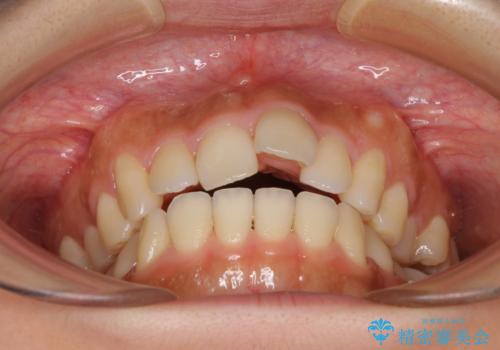

- 飛び出した前歯と口元の突出感を気にして来院された患者様です。

奥歯の咬み合わせを見ると、上顎が下顎に対して相対的に前方にありました。

口元の突出感を改善するためには、上顎臼歯を後方に移動させた咬み合わせにする必要があります。

インビザライン単体で改善することも可能ですが、達成する可能性が高くないため、カリエールディスタライザーという補助装置を併用して、より確実性を上げることとしました。

奥歯の咬み合わせを改善しながら、並行してインビザラインで歯列を整えることとしました。